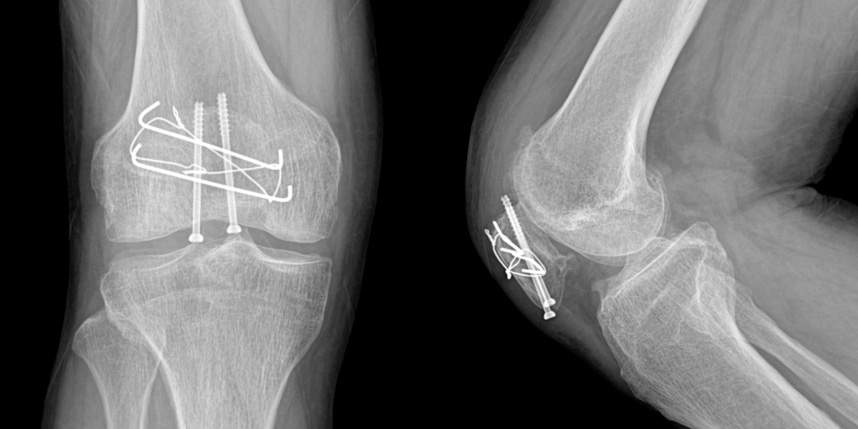

무릎 골절

골절이 심하지 않은 경우에는 깁스로 고정해서 유합을 시킬 수 있으나, 정도가 심한 경우에는 손,발목 골절 수술을 진행할 수 있습니다.

골절은 정확하게 골절편을 잘 맞추고 고정하는 것이 중요합니다. 특히 관절면을 잘 맞추는 것이 중요합니다.